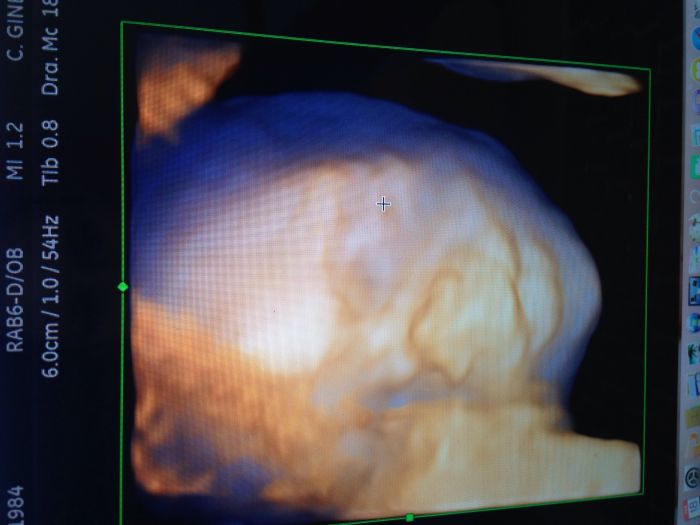

Já mám kontrolu zitra u mojí dr.a v pondělí v prenatalu velký UZ.už se těším!!!a chci si nechat potvrdit pohlaví,tak jsem zvědavá,jestli je to pořád kluk nebo uvidí holčičku

Jinak k tomu oblékání z porodnice také netusim zda bude stačit body nebo dlouhý rukáv nebo co jak Jíra je též prosincová tak to bylo podle me lehčí prostě ho nabalit :D Leni hezky FOTA a to otevřený ocicko supr :) K těm utz je to mazec jev za 16 TT ale je to tak pokud si nepriplatis pojistovna hradí max 3 za tehu :/